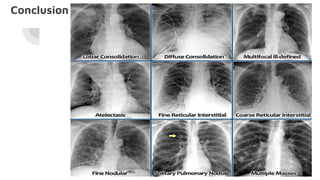

Pulmonary opacification patterns

Patterns

Linear pattern (Kerley

lines)

Nodular pattern Reticulonodular pattern Coarse reticulations &

honeycombing